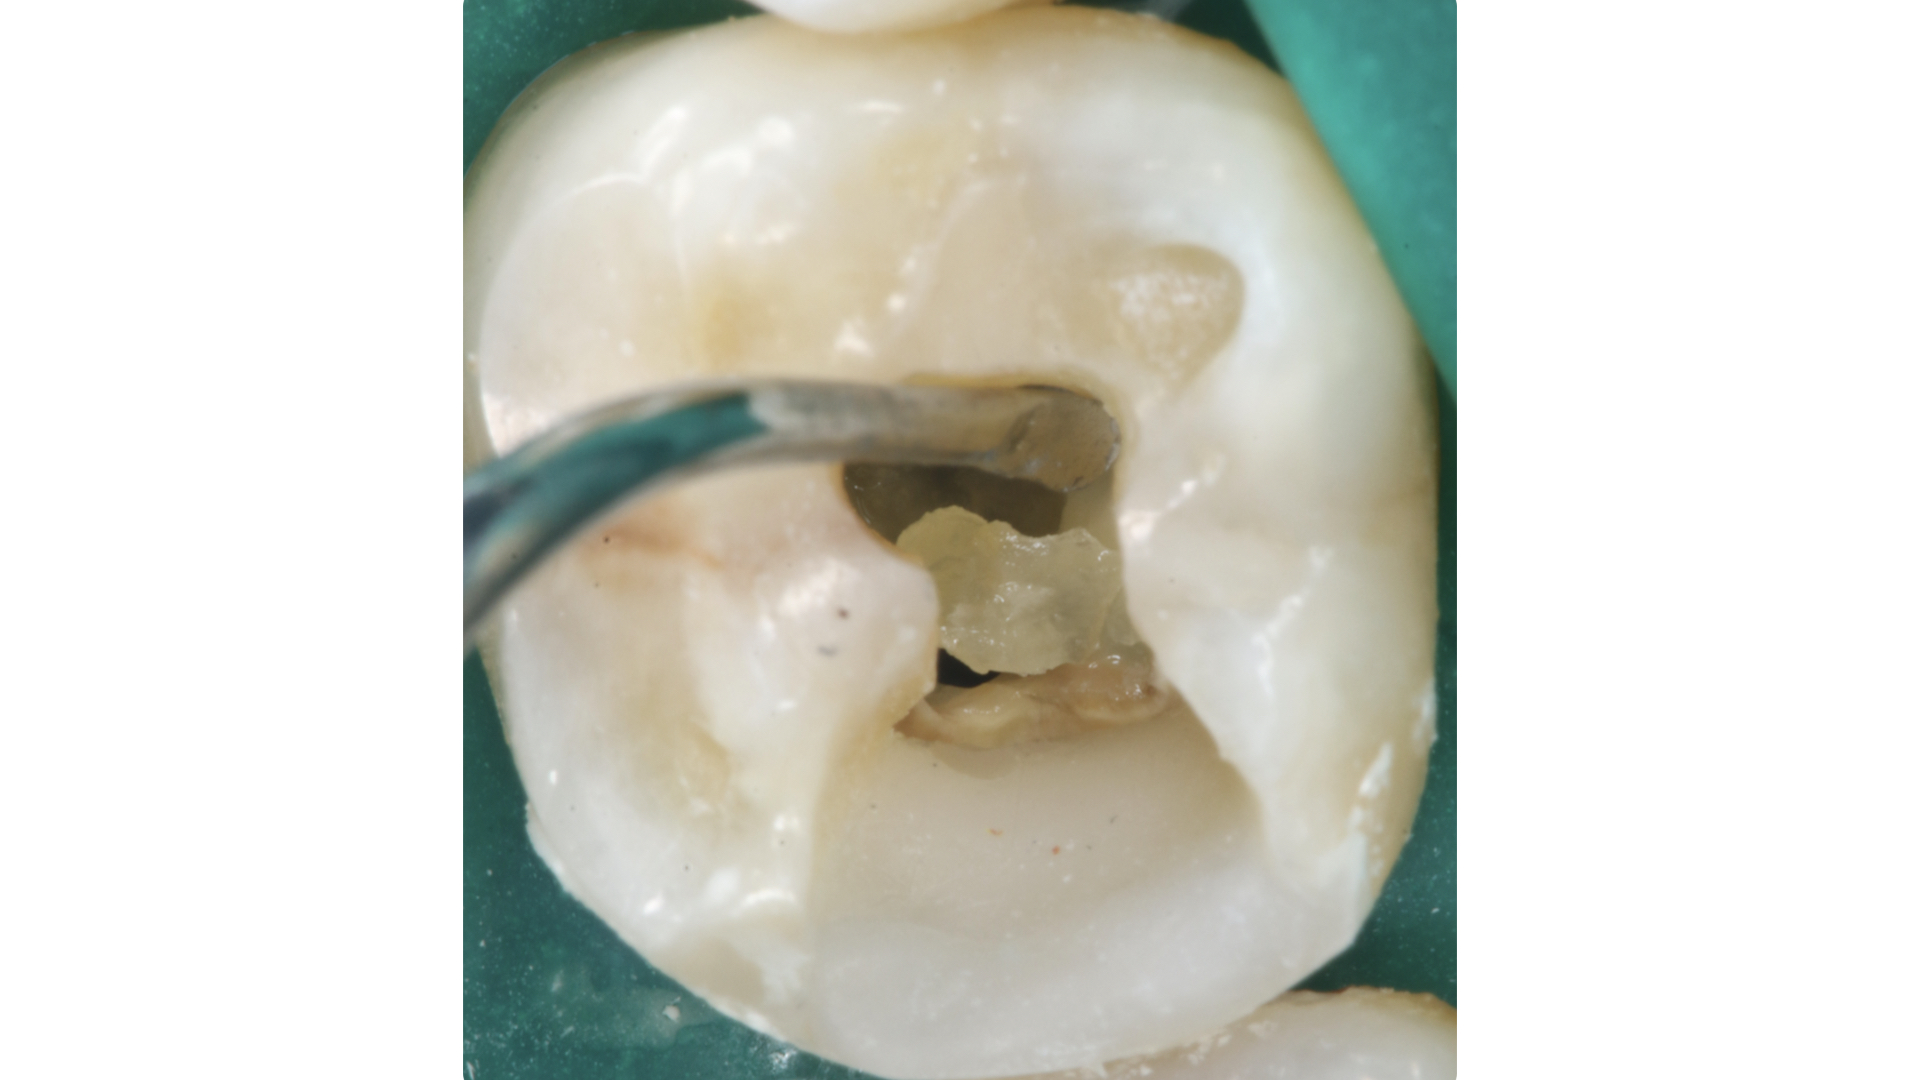

Il pavimento della camera pulpare si presenta sempre con un aspetto più scuro ed opaco rispetto al tessuto calcificato che tende ad essere lucido con un effetto che potremmo definire “vetrificato” (Figure 15-20).

Talvolta la differenza è evidente, in altri casi molto più sottile e quindi anche le difficoltà incontrate possono essere maggiori.

Asciugare la camera pulpare è il primo passaggio da compiere per poter visualizzare in modo netto le differenze.

A seguire l’utilizzo alternato di vari dispositivi a secco a bassi giri permette di distaccare ed eliminare i residui calcificati.